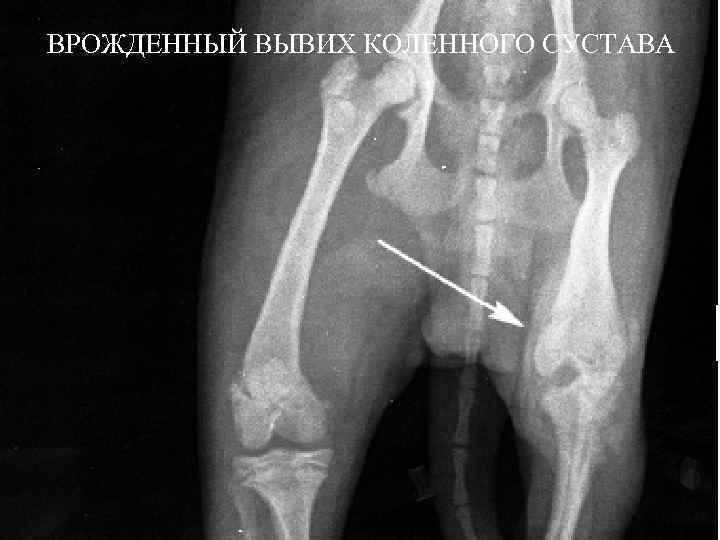

ВРОЖДЕННЫЙ ВЫВИХ КОЛЕННОГО СУСТАВА